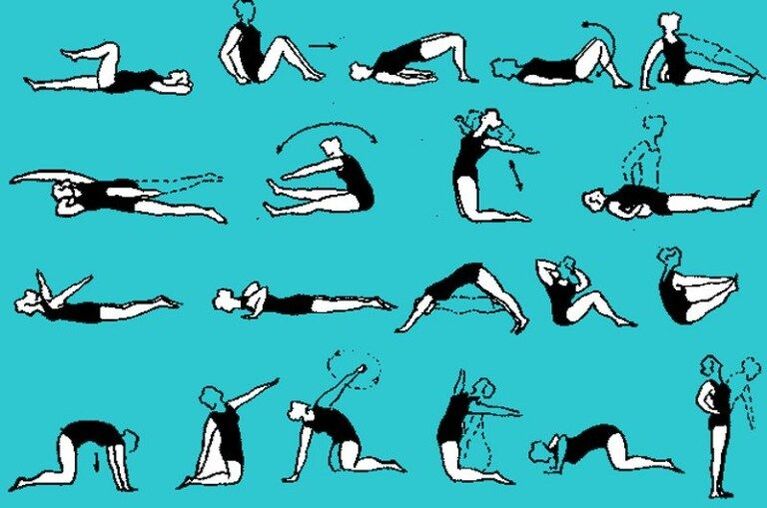

Terapeitiskā vingrošana

Osteohondrozes vingrinājumi ir iekļauti vispārējā terapeitisko pasākumu kompleksā. Vingrošanas terapija nodrošina palielinātu trofismu un ātru motoriskās aktivitātes atjaunošanu. Vingrinājumu kopums ir atkarīgs no bojājuma attīstības līmeņa un ilguma.

Vingrošanas terapijas priekšrocības:

- uzlabo metabolisma procesus;

- samazina spiedienu uz saknēm;

- koriģē stāju;

- Stiprina muskuļu ligamentālo aparātu.

Parasti kursa ilgums nepārsniedz divas nedēļas jebkura veida osteohondrozei.